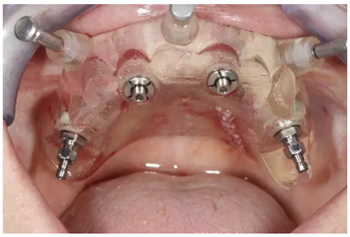

全程引導(dǎo)式手術(shù)

通過固位釘固定上頜NobelGuide外科導(dǎo)板和第一枚已植入的植體和導(dǎo)板基臺(tái)。

4枚NobelReplace CC RP4.3植體(11.5mm 軸向植體和13mm 傾斜植體)已植入完成:前牙區(qū)植體上裝配的是導(dǎo)板基臺(tái),后牙傾斜植體上裝配的是內(nèi)錐形連接的引導(dǎo)式持釘器。

使用內(nèi)錐形連接引導(dǎo)式持釘器在下頜前牙區(qū)植入NobelReplace CC植體。

4枚NobelReplace CC植體均已植入完成:前牙區(qū)植入NP 3.5*13mm植體并裝配引導(dǎo)式基臺(tái)以固定導(dǎo)板,后牙區(qū)植入RP4.3*16mm植體并裝配內(nèi)錐形連接引導(dǎo)式持釘器。